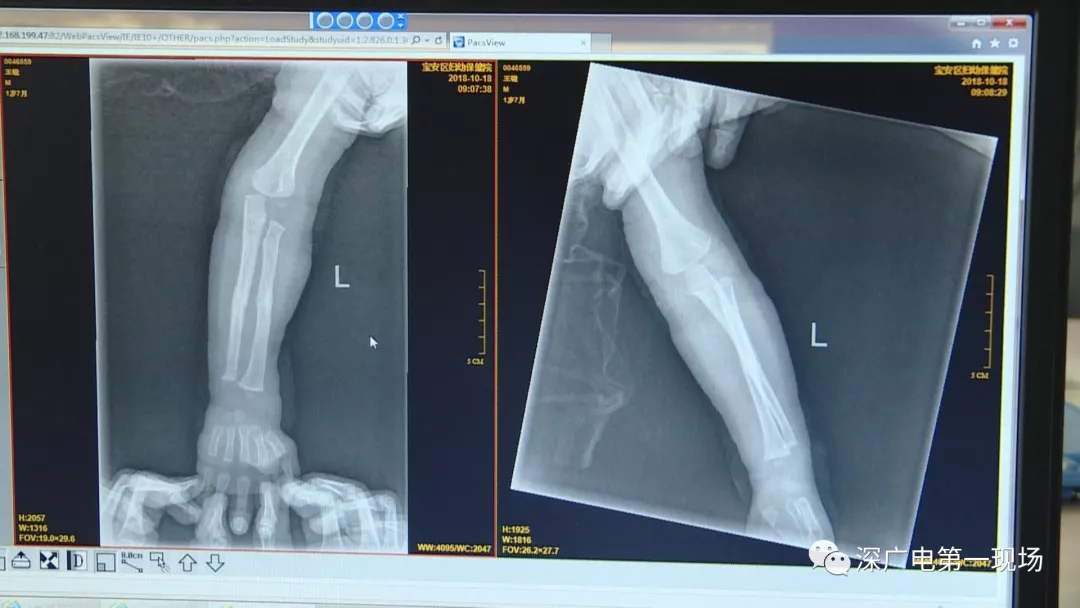

胳膊摔骨折胸片里發(fā)現(xiàn)異物